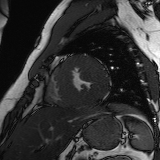

Refer to caption

Figure 2: Examples of tracking results using the proposed method (MPN-C). From left column to right: ED frame, ES frame, warped frame from ED, overlay of ES frame and the warped mask, and estimated motion field using HSV color coding. The color coding wheel legend indicates the motion directions.